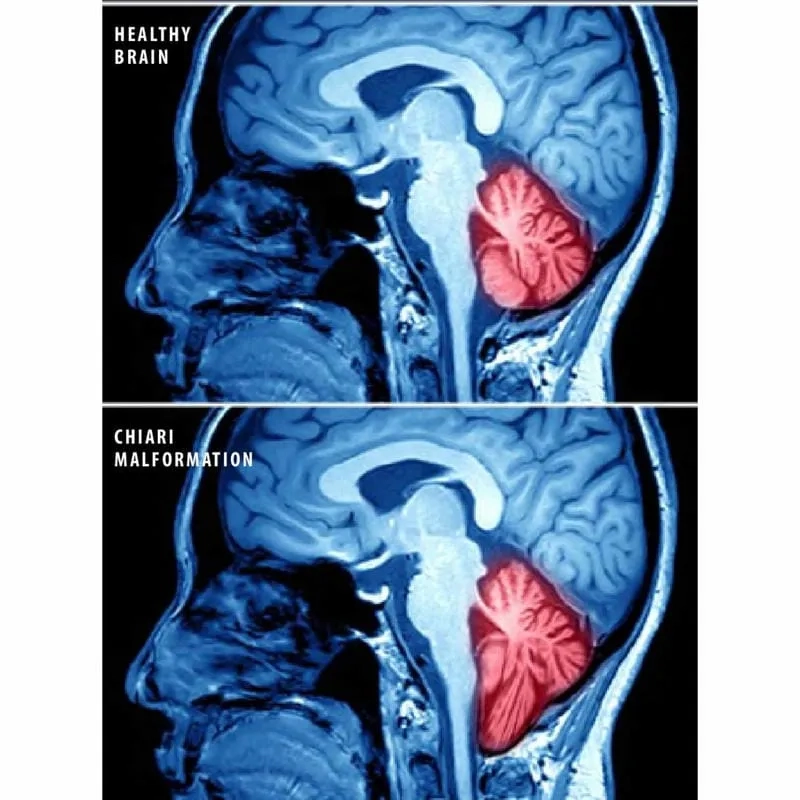

Understanding the different types of Chiari

• Chiari malformation is a structural defect in the cerebellum, the part of the brain that controls balance, and is usually present at birth.

• It occurs when a portion of the skull is smaller than normal, which pushes the cerebellar tonsils down into the upper spinal canal.